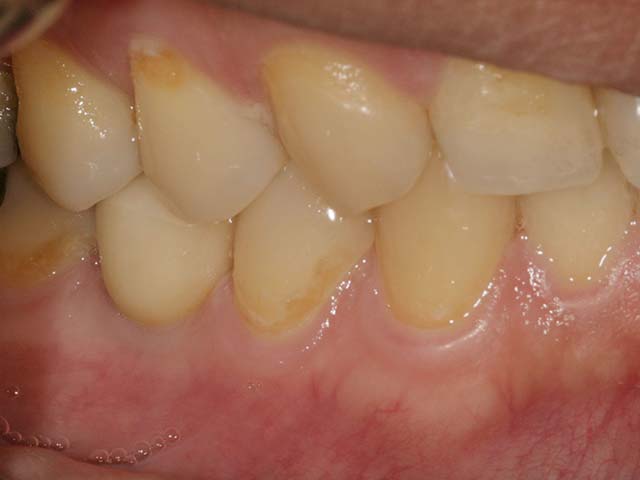

12年追蹤, 咀嚼與美觀功能良好